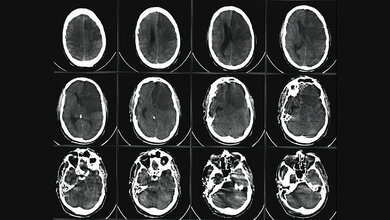

Probleme bei einem Schlaganfall

Wenn eine Verbindung aufgrund einer niedrigen Durchflussrate einmal sehr schwach geworden ist, kann dieser nur schwer wiederhergestellt werden. Ein häufiges Beispiel hierfür ist die Verstopfung eines Blutgefäßes, was im schlimmsten Fall sogar zu einem Schlaganfall führen kann. Bei einem Schlaganfall werden einige Blutgefäße in einer bestimmten Hirnregion durch die Verringerung des Blutflusses sehr schwach. „Wir haben festgestellt, dass in einem solchen Fall die Anpassungen im Netzwerk dauerhaft sind und auch nach der Beseitigung des Hindernisses beibehalten werden. Man kann sagen, das Netzwerk zieht es vor, den Fluss durch bestehende stärkere Verbindungen umzuleiten, anstatt schwächere Verbindungen neu zu bilden - selbst wenn der Fluss das Gegenteil erfordern würde“, erklärt Komal Bhattacharyya, Hauptautor der Studie.

Erinnerungsfähigkeit von Netzwerken

Mit diesem neuen Verständnis des Gedächtnisses von Netzwerken können die Forscher/-innen nun erklären, dass sich der Blutfluss auch nach erfolgreicher Entfernung des Gerinnsels permanent verändert. Diese Erinnerungsfähigkeit von Netzwerken ist auch in anderen lebenden Systemen zu finden: Der Schleimpilz Physarum polycephalum nutzt sein adaptives Netzwerk, um sich auf der Grundlage von Nahrungsreizen in seiner Umgebung zurechtzufinden, wie bereits in vorherigen Studien gezeigt wurde.